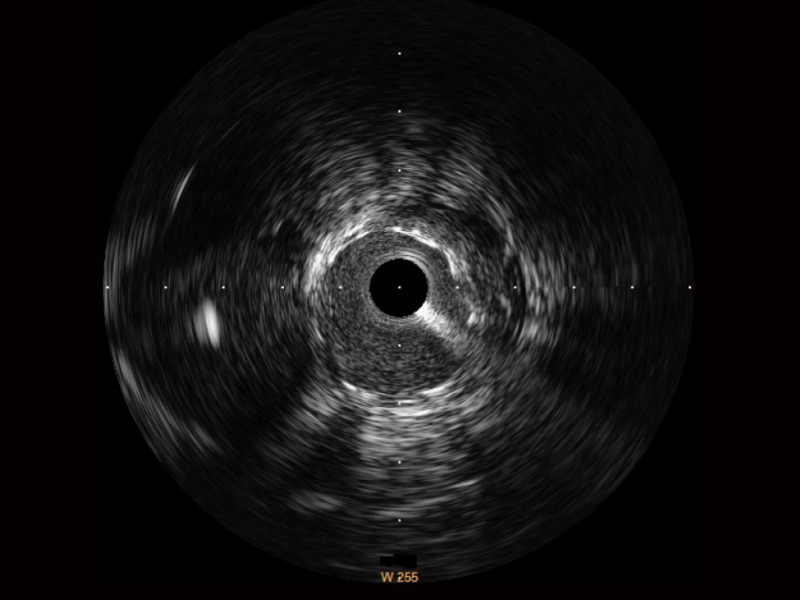

開立寬頻IVUS圖像

對比傳統(tǒng)IVUS導管成像,開立寬頻IVUS圖像的近場支架梁顯影更細膩,遠場中膜外血管仍清晰可辨,兼顧遠中近,兼顧分辨力與穿透深度